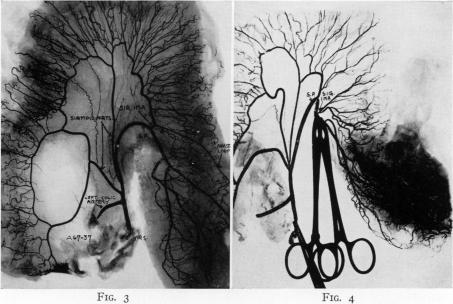

Blood supply of the rectosigmoid and rectum.

Ann Surg. 1950 Jan;131(1):100-8, illust. doi: 10.1097/00000658-195001000-00011.